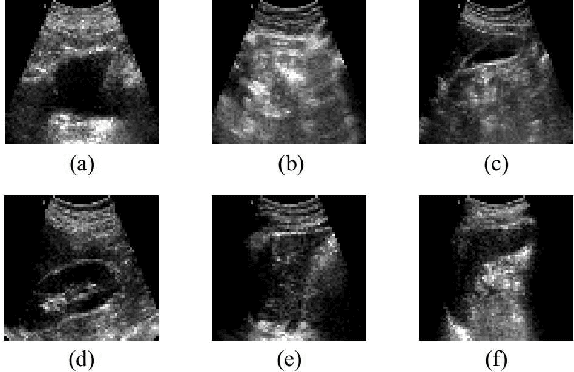

Abstract:Abdominal ultrasound imaging has been widely used to assist in the diagnosis and treatment of various abdominal organs. In order to shorten the examination time and reduce the cognitive burden on the sonographers, we present a classification method that combines the deep learning techniques and k-Nearest-Neighbor (k-NN) classification to automatically recognize various abdominal organs in the ultrasound images in real time. Fine-tuned deep neural networks are used in combination with PCA dimension reduction to extract high-level features from raw ultrasound images, and a k-NN classifier is employed to predict the abdominal organ in the image. We demonstrate the effectiveness of our method in the task of ultrasound image classification to automatically recognize six abdominal organs. A comprehensive comparison of different configurations is conducted to study the influence of different feature extractors and classifiers on the classification accuracy. Both quantitative and qualitative results show that with minimal training effort, our method can "lazily" recognize the abdominal organs in the ultrasound images in real time with an accuracy of 96.67%. Our implementation code is publicly available at: https://github.com/LeeKeyu/abdominal_ultrasound_classification.